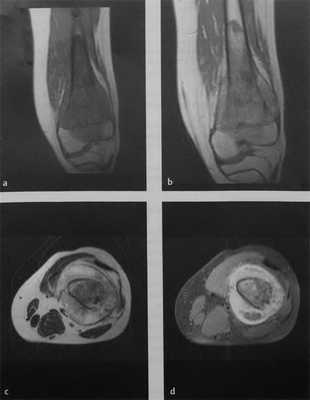

![Снимки МРТ и КТ. Остеосаркома]()

а-d МРТ того же пациента: а) Фронтальное неконтрастное Т1 -взвешенное изображение; b) Фронтальное Т1 -взвешенное изображение после введения контрастного вещества. Негомогенное накопление контрастного вещества костным и мягкотканным компонентами опухоли; с) Аксиальное неконтрастное Т2-взвешенное изображение последовательности турбо ТSЕ. Распространенная опухолевая инфильтрация мягких тканей вокруг диафиза бедренной кости. Отсутствие вовлечения сосудов бедра опухолью; d) Аксиальная Т1 -взвешенная последовательность с подавлением МР-сигнала от жировой ткани после введения контрастного вещества.